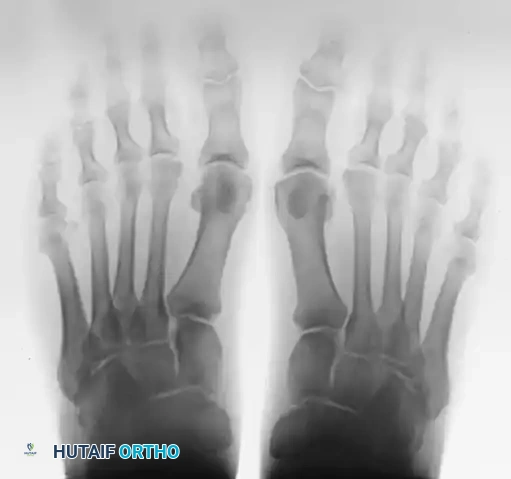

The oblique view is critical for profiling the fibular sesamoid.

FIGURE 81-100 B: Oblique view profiles the fibular sesamoid. Note the cystic fibular sesamoid on the right foot. This probably represents an old fracture through the syndesmotic union of a bipartite sesamoid.